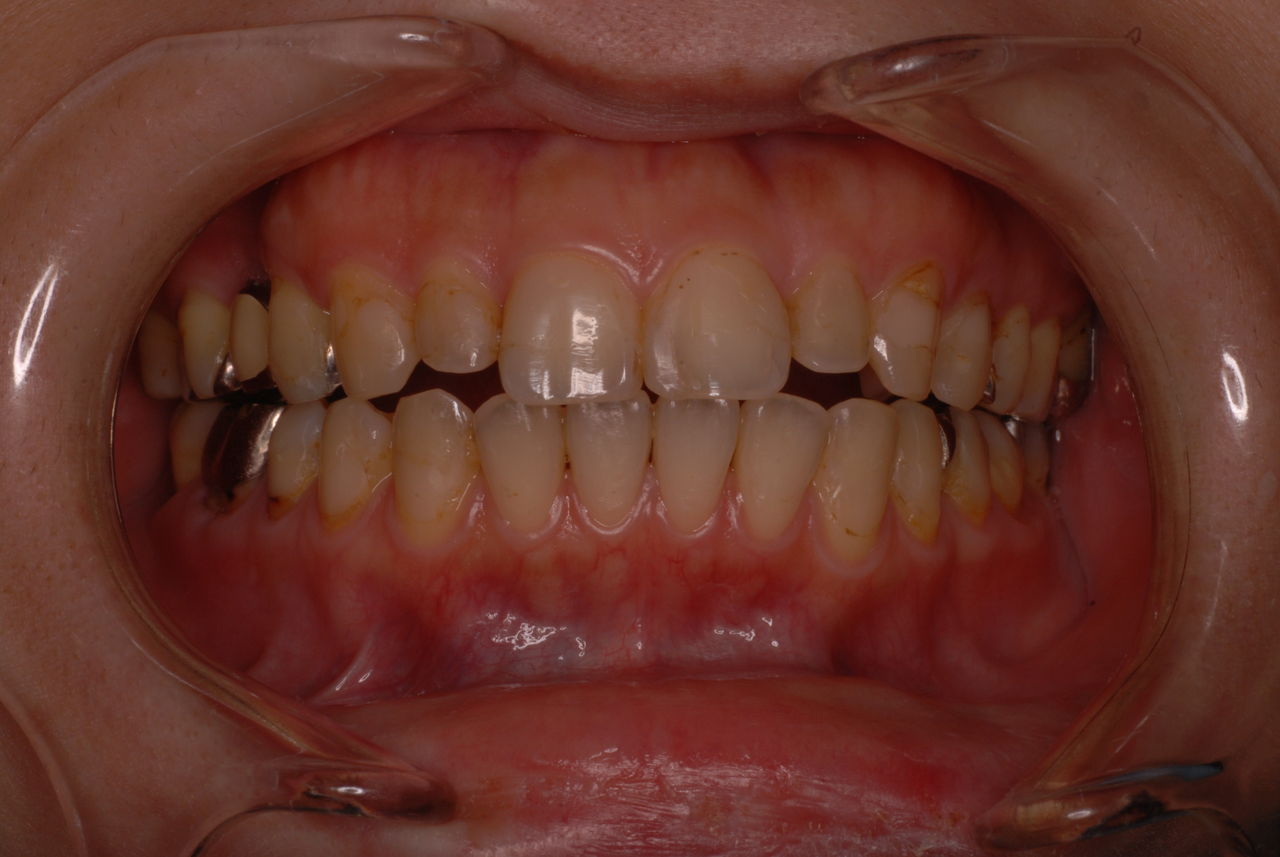

親知らずを取ることを嫌がる方が多いのですが、もし親知らずとその隣の14歳大臼歯の間に虫歯ができたり歯周病を罹患した場合、どれほど治療が大変で再発も起こりやすいか理解できない方がおおいのです。

写真左下の親知らずが痛くなり抜歯しました。その後歯茎を除去して虫歯を露出させる処置を二回ほどしています。